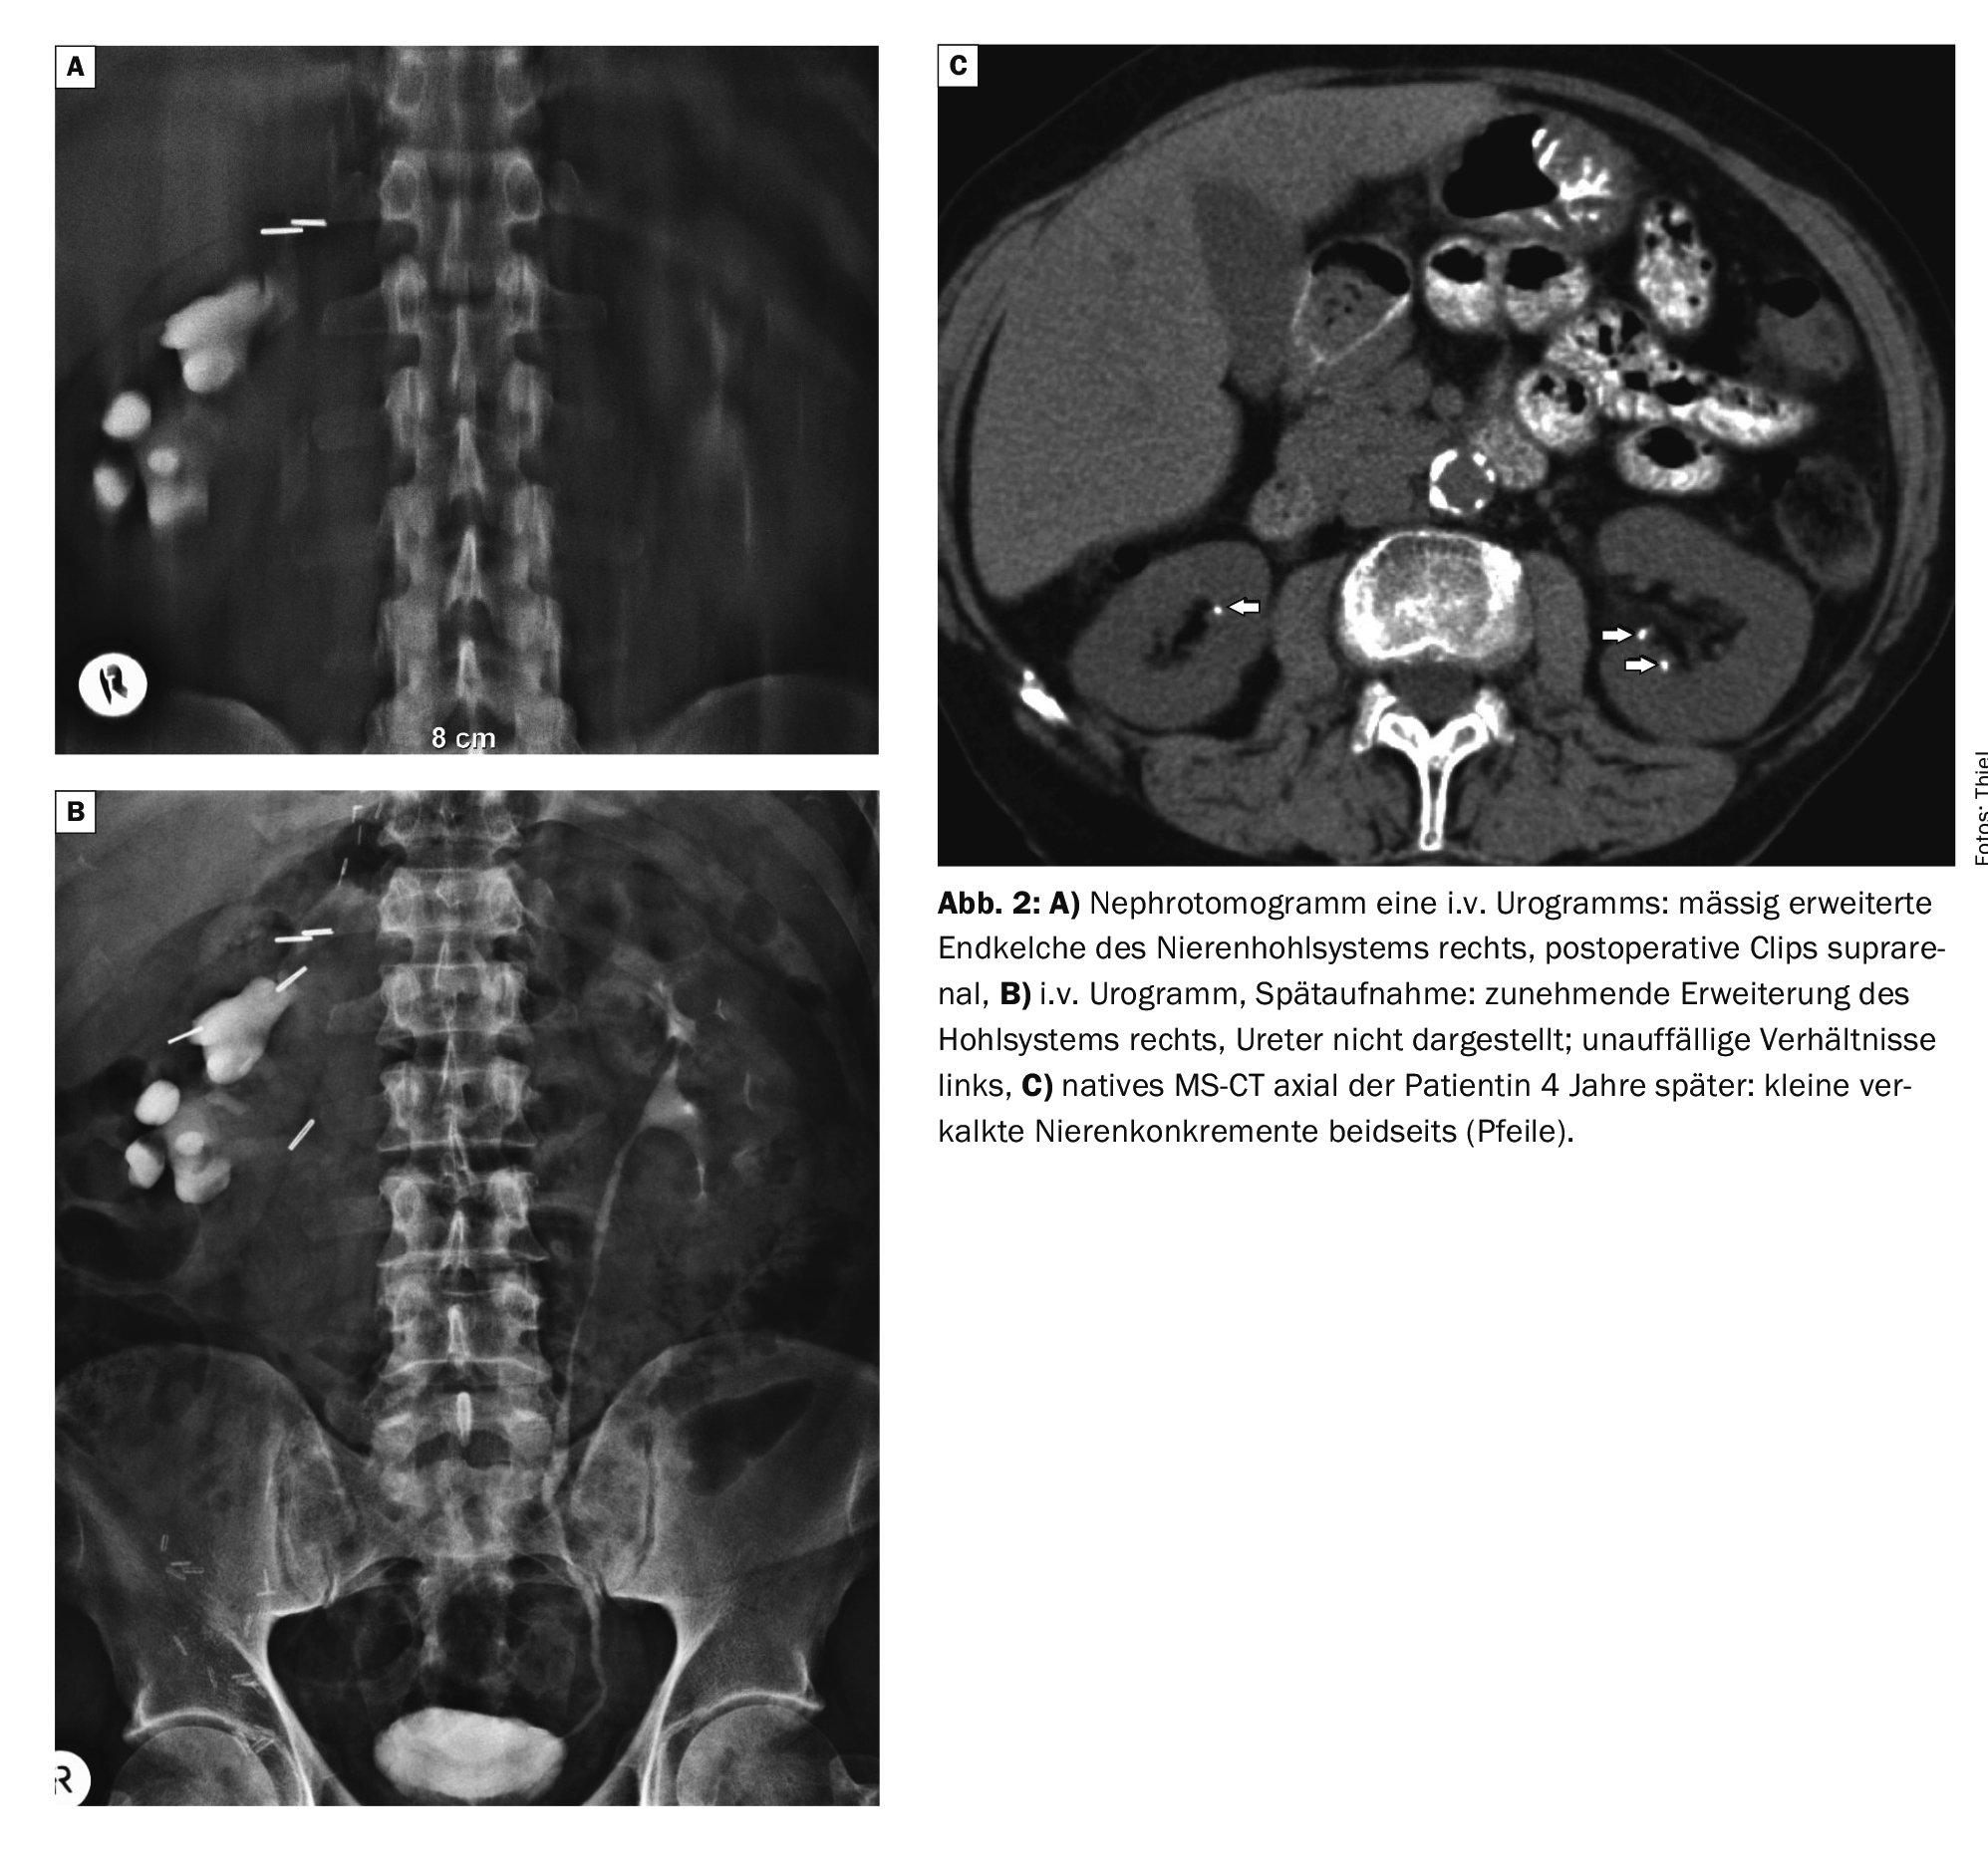

Case 2 shows images of an i.v. urogram with tomogram in a then 79-year-old female patient, hardly common today. Z.n. adrenocortical carcinoma, numerous suprarenal clips. A moderate dilatation of the terminal calyces on the right side with unremarkable findings of the left kidney was conspicuous. Four years later, recurrent bilateral flank pain on CT showed small calcified kidney stones in both kidneys (Figs. 2A to 2C).